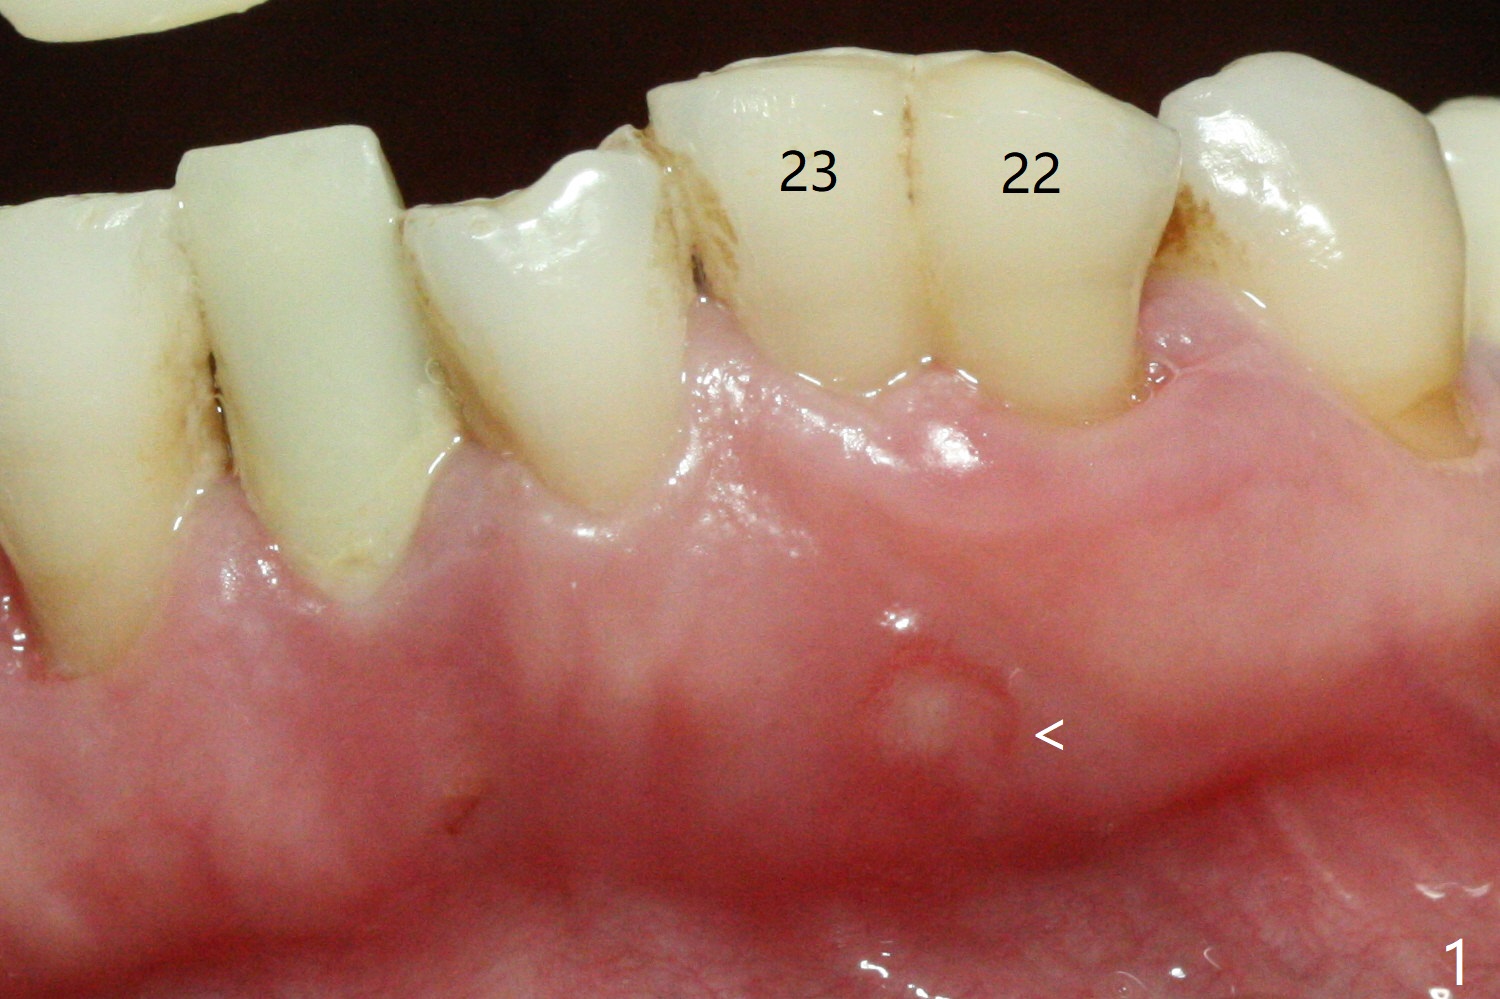

There is a fistula buccal to the apex of the tooth #23 preoperatively (Fig.1), which is related to loss of the buccal plate of the socket of #23. Therefore an implant is placed mainly in the socket of #22 (Fig.3). The lingual (Fig.2 L) gingiva appears to have more extensive inflammation. After extraction, the lingual (Fig.3 L) gingival margin is significantly lower than the buccal one. The lingual crest is ~ 4 mm lower than the buccal one. A 3.8x10 mm dummy implant is placed tentatively with an apical space (Fig.4). When a same dimension definitive implant is placed with 40 Ncm, it is 2 mm below the lingual gingival margin, whereas 6-7 mm below the buccal one (Fig.5). Vanilla graft is placed before placement of a 5.5x4(5) mm abutment (Fig.6,7). There is a 2-3 mm lingual (L) gap to be filled with the allograft secondarily to prevent periimplantitis (Fig.7). Later the abutment is changed to a longer and smaller one (Fig.8) with more of the allograft (*). After trimming of the abutment (Fig.9 (*: papilla between the fused teeth)), an immediate provisional is fabricated to close the socket (Fig.10, similar to Fig.1). The majority of the bone graft seems to be in place 8 months postop (Fig.12). The implant appears to have been placed buccal, consistent with the thin and slightly erythematous buccal gingiva (Fig.13). The ridge completely regenerates 2 years post cementation (Fig.14).